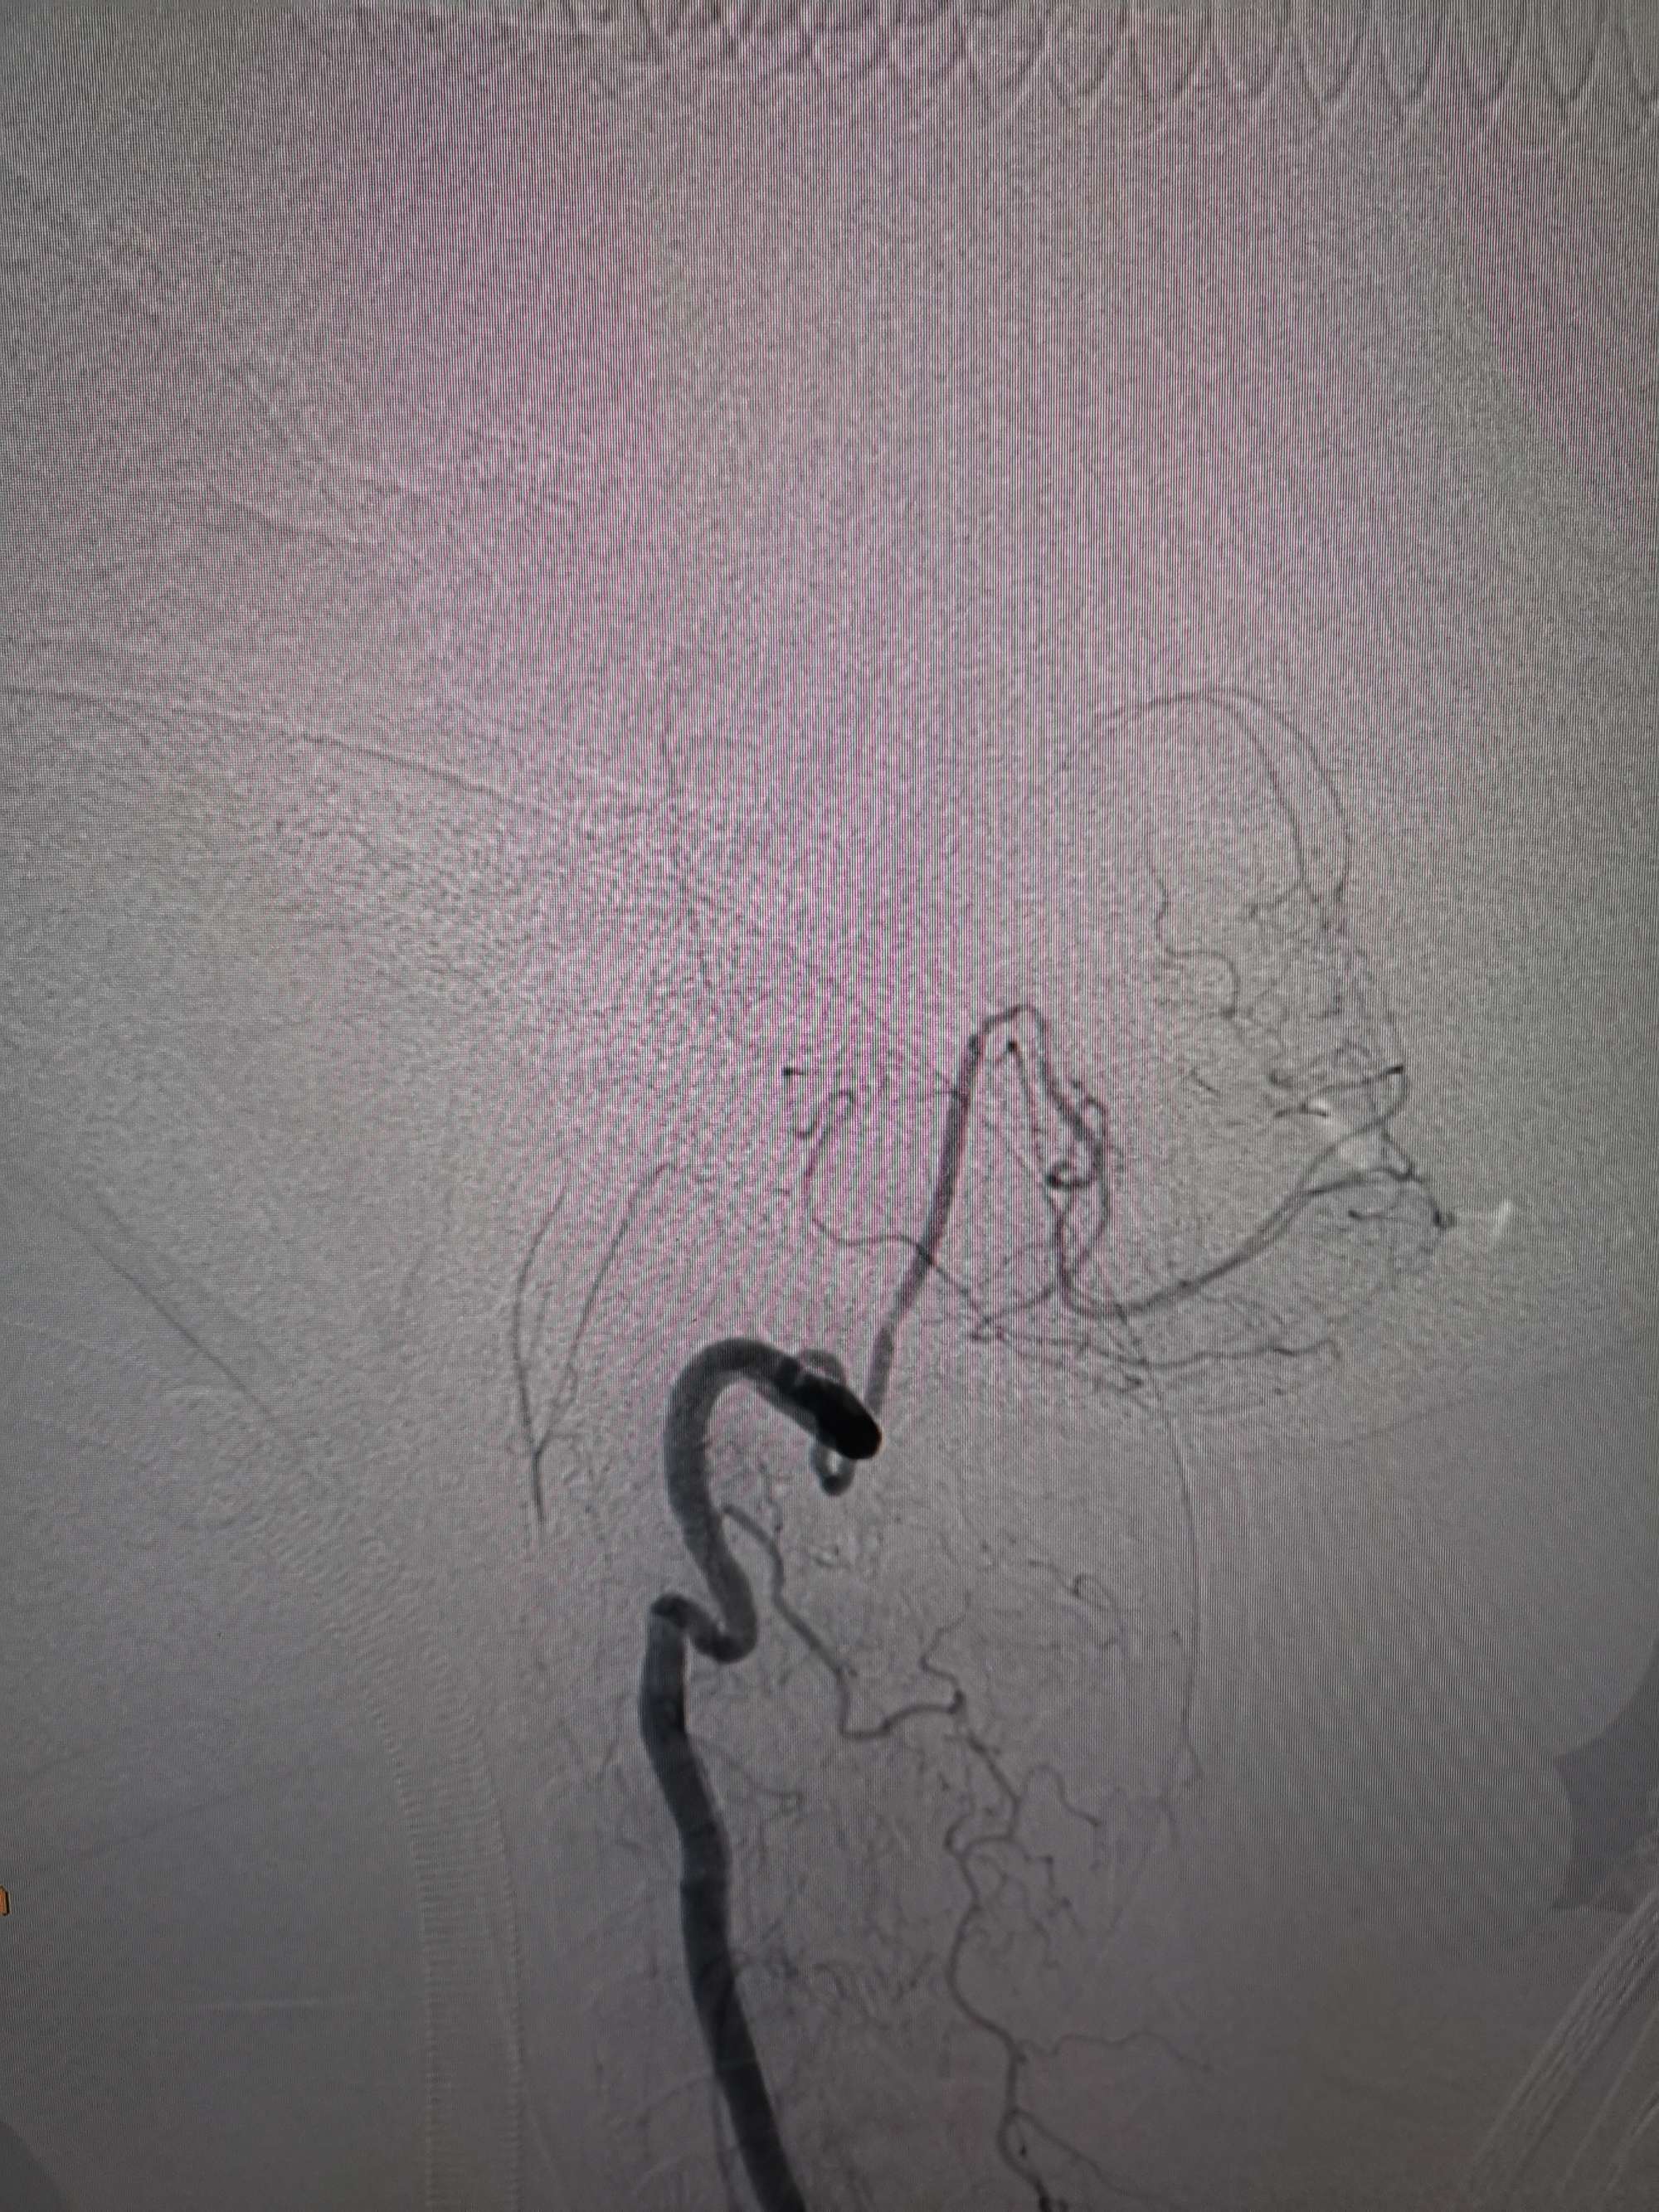

因患者左侧椎动脉自PICA以远完全闭塞,右侧椎动脉经穿支仍向基底动脉有少量供血,故决定开通左侧椎动脉。

因患者发病已6周,术前需重新评估血管代偿情况。

术前再次造影评估

右侧椎动脉穿支供血及左侧PICA供血较入院时略有改善,但改善不明显。故按计划行左侧椎动脉再通术